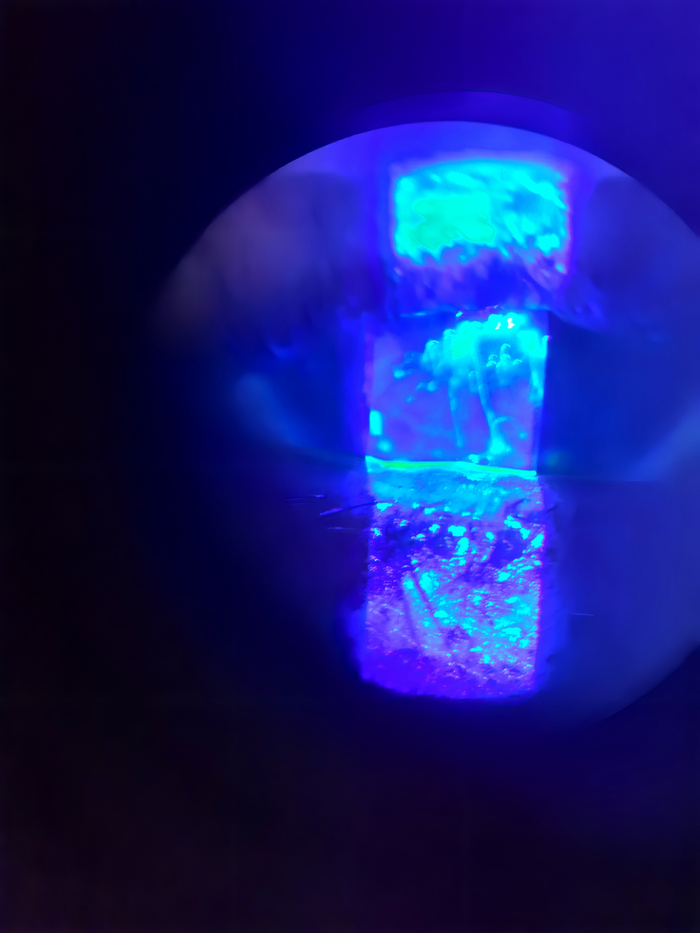

Азелаиновая кислота работает как тихий диверсант. Она проходит внутрь бактериальной клетки через специальные ионные транспортёры (такие белковые ворота в мембране) и понижает pH — делает среду более кислой. Чем кислее становится среда, тем охотнее бактерия втягивает ещё больше кислоты.

Примерно так:

Она как бы сама себя топит. Дальше кислотность рушит протонный градиент (разницу концентрации протонов, за счёт которой клетка вырабатывает энергию), и кислота начинает вмешиваться сразу в несколько контуров. Она бьёт по ферментам дыхательной цепи (клетка не может вырабатывать энергию), блокирует переработку глюкозы (нет питания), останавливает производство строительных блоков ДНК (нет размножения). Нет энергии — нет деления. Нет ножек — нет мультиков. Секрет устойчивости к резистентности вот в чём: чтобы выжить, бактерии пришлось бы переписать саму свою физиологию, а это уже не мутация, а полная перестройка.